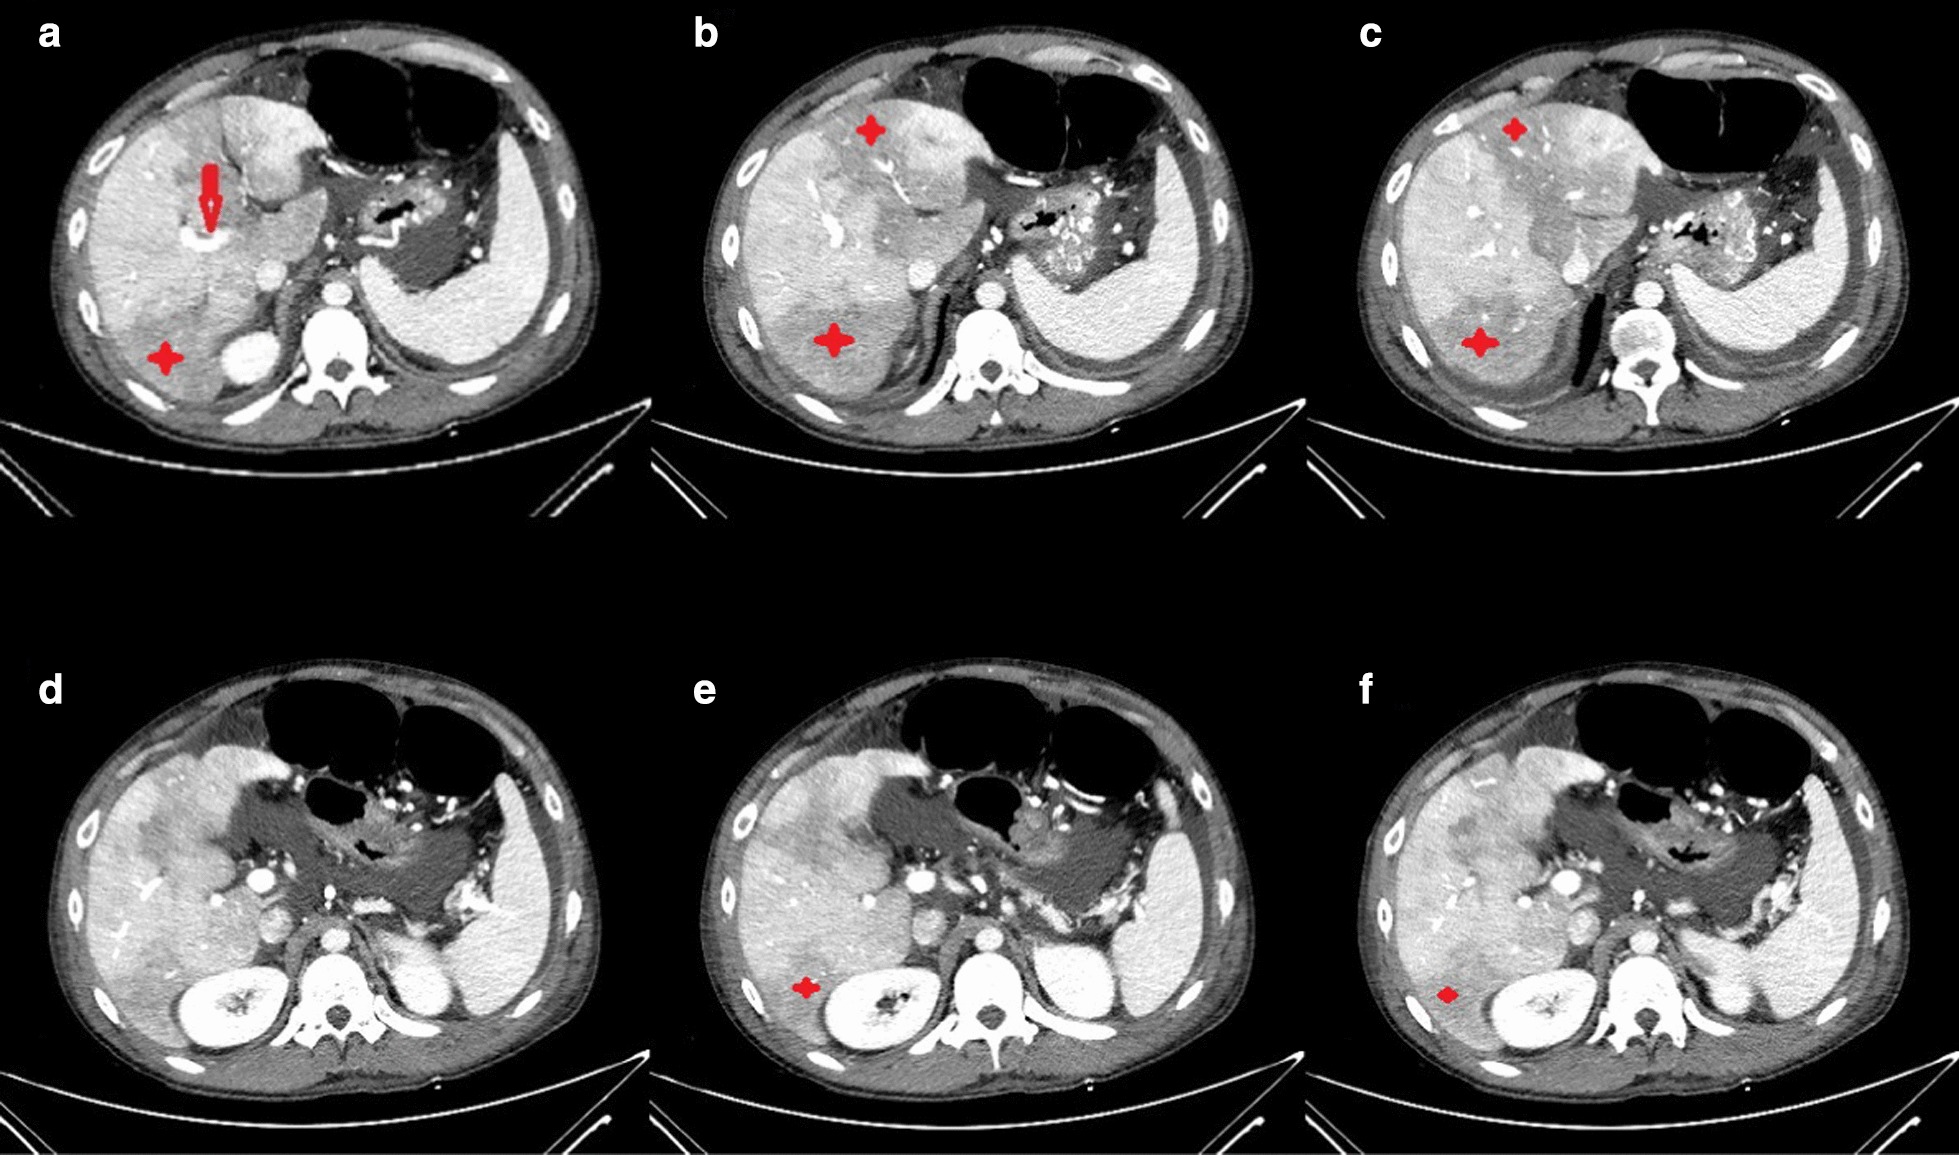

Regarding concomitant abdominal pain and abnormal liver biochemistries (Table 2), abdominal CT was requested which showed hypoperfused areas in the posterior segment of the right (Rt.) hepatic lobe and the medial and lateral segments of left (Lt.) lobe along with evidence of filling defect in the main Rt. Portal vein. Also, the Lt. portal vein was not opacified (Fig. 2). Color Doppler Sonography (CDS) of the abdomen showed the absence of flow in the portal vein without collateral veins consistent with acute portal vein thrombosis. An extensive evaluation of the possible underlying hypercoagulable state was unremarkable (Table 3).

Fig. 2.

Abdominopelvic CT with IV contast. Hypoperfusion is seen in the posterior segment of right (Rt.) hepatic lobe, and the medial and lateral segments of left (Lt.) lobe (stars). Evidence of filling defect in main Rt. portal vein is also detected (arrow)